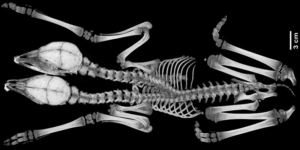

De Siamese tweeling had twee gescheiden hoofdjes en nekwervels. Ook een deel van de ribben, borstwervels en bovenste deel van het borstbeen waren gescheiden. Achter de 9e borstwervel deelden de Siamese tweeling de wervelkolom. Ook bij de organen werden sommige organen gedeeld, zoals de lever, en waren andere wel gescheiden, zoals de slokdarm. Bijzonder was ook dat het kalfje weliswaar twee harten had, maar deze samen in één hartzakje zaten. Het kalfje is doodgeboren, hetgeen afgeleid werd uit het zinken van stukjes long die in water werden gelegd.

| CT-scan van het skelet (links) en foto van de organen (rechts). Foto: Gino D’Angelo et al. University of Georgia | |